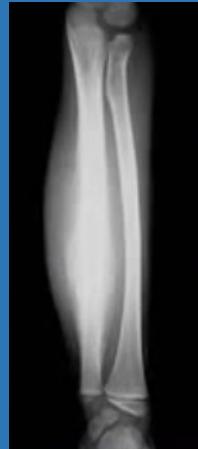

| Compartment Syndrome | Increased pressure within a closed fascial compartment, leading to reduced tissue perfusion, hypoxia, and irreversible muscle and nerve damage. Causes: Fractures (especially tibia/forearm), severe soft tissue trauma, arterial injury, burns, tight casts/dressings, post-ischemic reperfusion swelling, IV fluid extravasation, and bleeding disorders (e.g., hemophilia). High-Risk Notes: Pain may be absent in altered consciousness, children (monitor analgesia response), polytrauma, sedated/epidural cases, or concomitant nerve damage. Open fractures do not always decompress pressure. Gross/Clinical: -tense, shiny leg swelling with blisters in compartment syndrome.Imaging: - Intraoperative fasciotomy | History/Symptoms: Pain out of proportion to the injury (e.g., a “bursting” sensation), which is not relieved by analgesia. Clinical Features (The 5 P’s): - Pain with passive stretch (early, key sign; e.g., ankle dorsiflexion for leg, wrist for forearm). - Paresthesia (early). - Palpable tense swelling (shiny skin, blisters: clear=mild, serosanguinous=severe, bloody=worst; dusky/pallor skin). - Pallor, Paralysis, Pulselessness (late, ominous signs; pulses often palpable until late). Investigations: Primarily a clinical diagnosis (high suspicion key). Compartment pressure measurement can confirm: absolute pressure >30 mmHg or Delta Pressure (Diastolic BP - Compartment P) ≤ 25 mmHg. | Initial: ABCs, supplemental oxygen. Remove all circumferential dressings, casts (bivalve to skin), and splints. Elevate the limb to heart level (not above; higher reduces inflow). Correct any hypotension. Surgical: Urgent Fasciotomy if no response within 1h or confirmed pressure (prophylactic in high-risk like major osteotomy). Release all compartments/skin with long incisions; debride necrotic muscle via 4C’s (early: pink/red, soft, contracts/bleeds on pinch; late: dark, firm, no response); preserve neurovascular. Wound open (bulky dressing/splint, VAC, or boot-lace gradual closure); repeated inspections x48h; coverage in 3-5 days (skin graft usual; flap if nerves/vessels/bone exposed). | Cellulitis, Deep Vein Thrombosis (DVT), Arterial occlusion, Severe soft tissue injury without compartment syndrome; equivocal cases in polytrauma. | Complications: Volkmann’s ischemic contracture (permanent deformity, weakness, sensory loss, chronic pain). Contraindications (Fasciotomy): Confirmed >48h (irreversible damage, high infection risk from dead tissue); crush injuries with already necrotic muscle. |

| Open Fracture | A fracture with a breach in the overlying skin and soft tissues, creating communication with the external environment. All open fractures are considered contaminated (even small punctures; aka compound fracture). Causes: Can result from high-energy trauma (RTAs, falls, firearms; signs: degloving, crush syndrome, bone loss, segmental) or low-energy trauma. Contamination risk higher with farm/soil injuries, bites, delayed presentation (>12h), fecal/oral/soil/water exposure. Mechanism: Low/high velocity missiles (cavitation >300 m/s); in-out (cleaner) vs. out-in (dirtier). Gross/Clinical: ![]() | History: Mechanism of injury (energy, time, place, type/impact method), consciousness, wound size/bleeding amount, other injuries (often missed), tetanus status. Assessment: ATLS protocol (ABCDE) first (treat patient, not fracture; exclude shock/brain injury, monitor vitals; viscera exam: ribs=lungs/liver/spleen, pelvis=bladder/urethra). Examine wound (look/feel/move carefully post-splint), check distal neurovascular status, compartment syndrome. Photograph/remove gross contamination; cover with saline dressing. Classification (Gustilo-Anderson): - Type I: <1 cm wound, clean, minimal soft tissue. - Type II: >1 cm wound, moderate soft tissue (no stripping). - Type IIIA: Extensive soft tissue damage, but adequate bone coverage. - Type IIIB: Extensive soft tissue loss with periosteal stripping; bone exposed, requires flap coverage. - Type IIIC: Any open fracture with an arterial injury requiring repair. | Initial (ER): ATLS first. Cover wound with sterile saline-soaked dressing, splint limb, IV fluids (request blood if needed); traction if no distal pulse/deformity. Prophylaxis: Tetanus prophylaxis/serum and broad-spectrum IV antibiotics immediately (culture tissue/blood); clean major contamination. Surgical: Urgent debridement/irrigation within 6-12h (“Dilution is the solution to pollution”; pulse-irrigate 3-6-9L saline; excise non-viable tissue/foreign material, trim skin edges, remove dead muscle/detached bone, preserve N/V). Stabilization: external fixator (preferred severe; replace with cast post-infection); internal if clean/minimal. Wound closure delayed (primary if small/clean; secondary if contaminated/large). Early soft tissue cover. | The diagnosis is typically obvious. Key: Classify severity; identify associated injuries like compartment syndrome, vascular damage, or high-energy signs (e.g., crush). Differentials for contamination: Primary (field debris) vs. secondary (post-fixation if poor debridement). | Complications: Infection (cellulitis, osteomyelitis, chronic with sequestra/drainage, gas gangrene), tetanus; higher with delay/exposure/bites. - embolisms fat, thrombi others.. Case Insight: Unconscious patient (e.g., open tibia post-RTA): ABCDE/cervical collar, distal pulses/traction, admit for debridement; ankle fall: Splint post-ABC, assess neurovascular. |